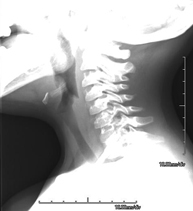

- Cervical spine X-ray

This technique uses X-ray rendered imaging for examining the cervical spine. Indicated for: trauma, cervical pain.